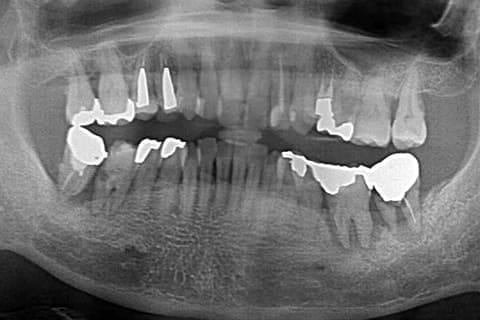

CASE.01 「サイナスリフト法」

-

- 治療内容

- サイナスリフト法

- 治療費用

- ¥220,000